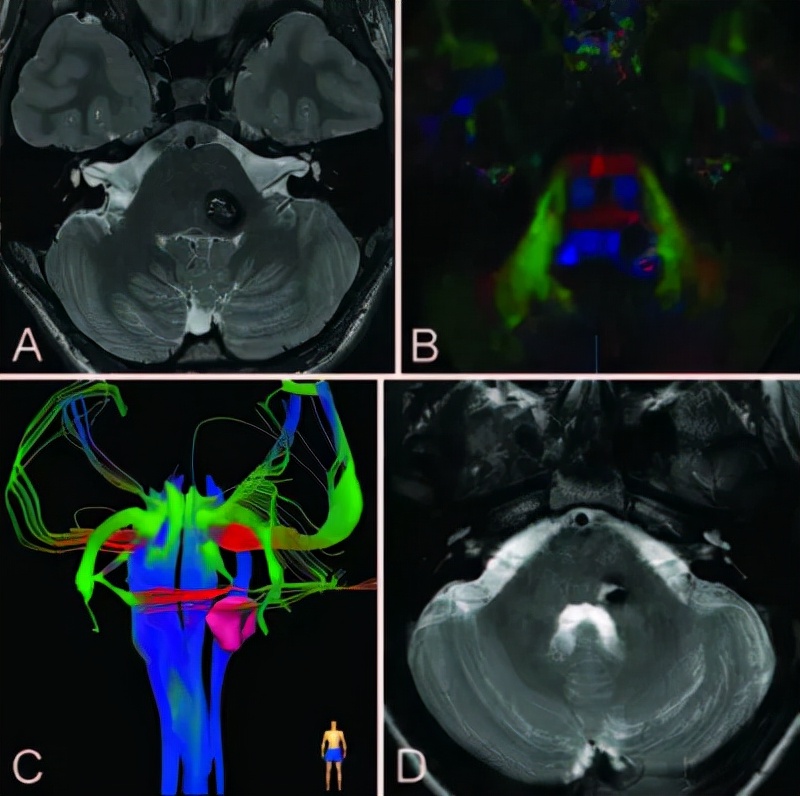

一个36岁高中老师,本该是在三尺讲台、诲人不倦、春风化雨的美好岁月,但却查出有脑干海绵状血管瘤,曾有两次脑干出血,两次都是保守治疗后症状消失,一次次幸运的死里逃生后,于是对这病似乎也没有放在心上,更彻底的手术治疗也一拖再拖,没想到,一年时间不到,他突然又爆发头痛、连路也走不稳了,查出又是脑干出血,但这一次,因为出血量太大,他留下了偏瘫的后遗症,也终于明白,这样下去不是办法,只有手术全切这个病变才能彻底治愈。

脑干出血3D示意图

4 脑干海绵状血管瘤

恶化几率: 脑海绵状血管瘤一般无良恶性之分,但当其生长在脑干、丘脑、基底节、延髓等部位会极其危险,随时可能出现出血。以脑干出血为例,出血量少于3ml死亡率70%,5ml以上死亡率90%左右,而超过10ml则死亡率达到100%,未出过血的脑海绵状血管瘤年出血率为0.6%,但是出过一次血的脑海绵状血管瘤年出血率高达4.5%~22. 9%,反复出血的患者年出血率更高,所以患者尤其需要警惕。

治疗策略:手术切除病灶是治疗海绵状血管瘤的根本方法。治疗上应合理选择手术入路尽可能地安全全切病灶,将出血风险降到最低,这是治疗取得成功的关键。病变全切除可获得治愈效果。治疗的难度在于,脑干手术风险极大,90%可能性会发生脑干并发症,手术治疗的预期可能不手术还糟糕。

最佳手术时机:当患者出现明显的症状或者活动性出血(即使只有一次)的情况下,要想根治海绵状血管瘤引起的反复出血手术治疗是患者唯一的选择。否则脑袋中的那个“不定时*弹炸**”随时可能爆发——可怕的脑干出血谁也不知道哪一天会比明天先来到,等那时候一切为时已晚。